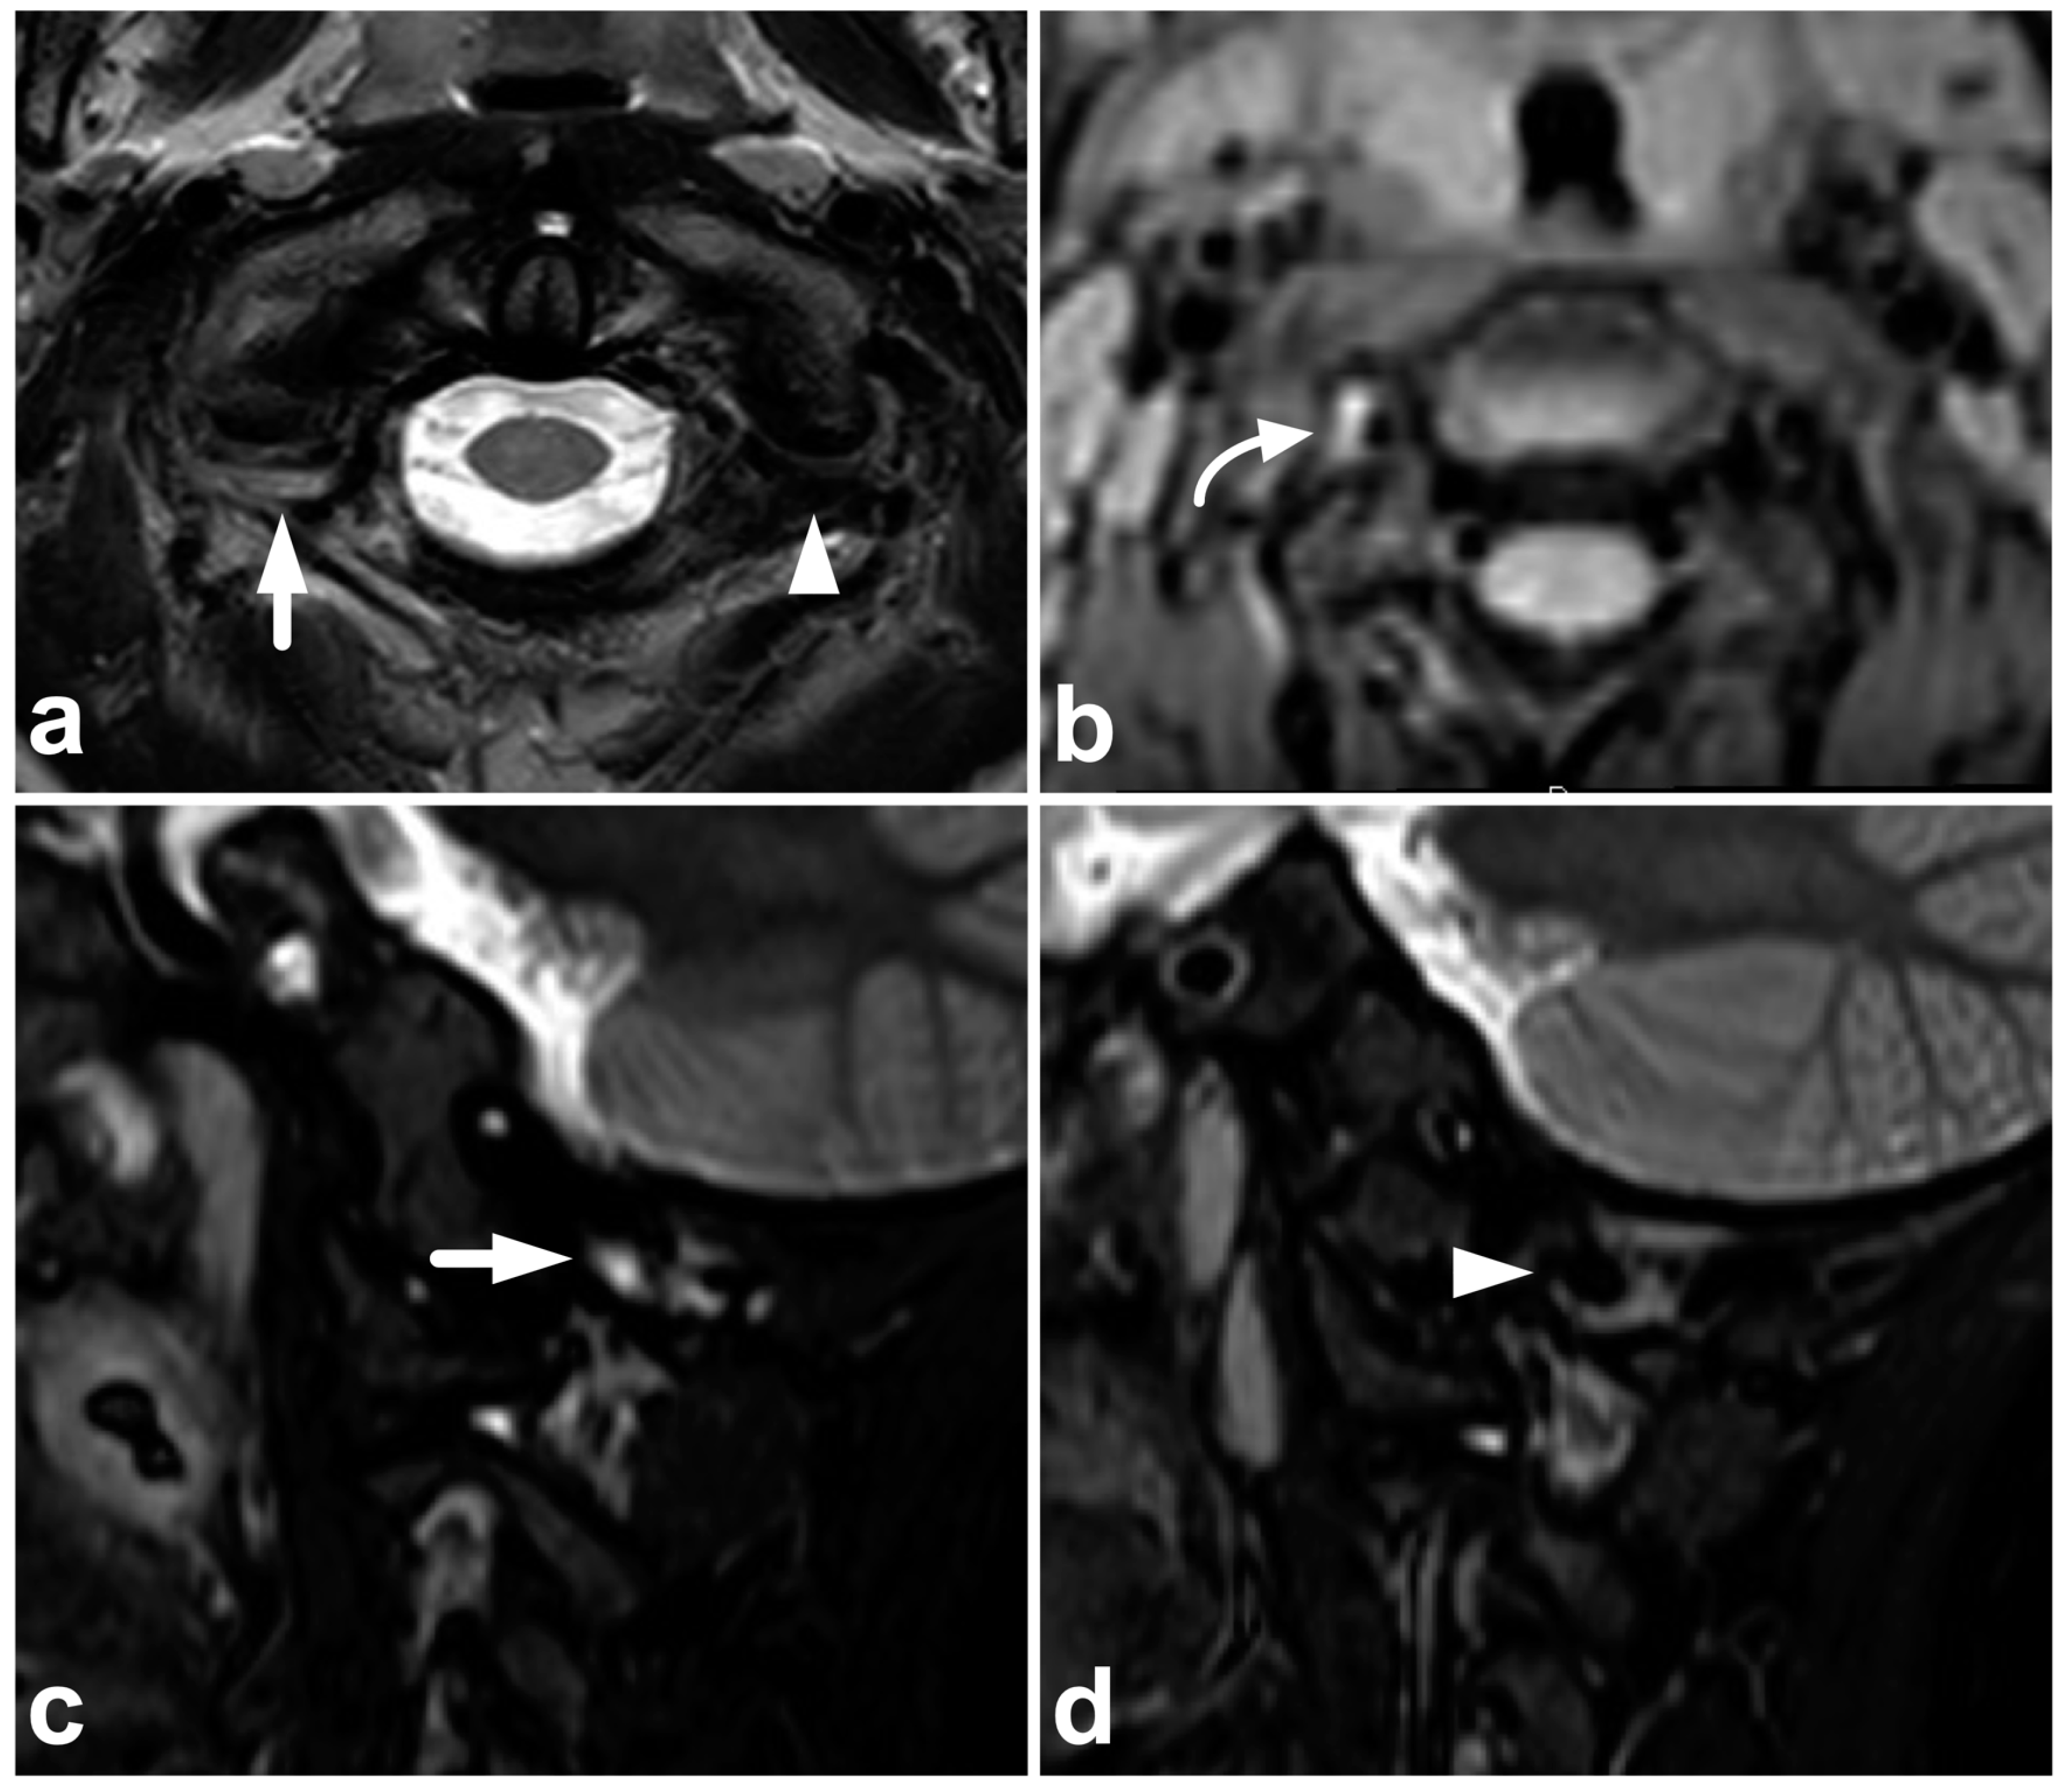

4.1. Occipitocervical and Atlantoaxial Ligaments

4.2. Posterior Ligament Complex

4.3. Anterior and Posterior Longitudinal Ligaments